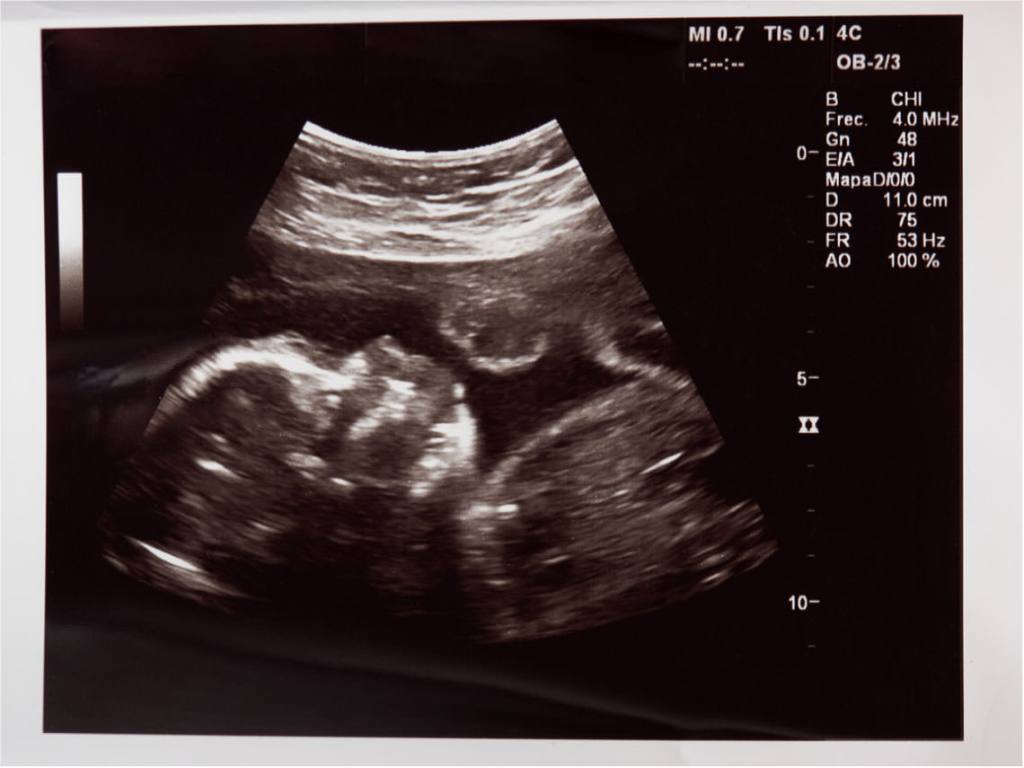

Entre las semanas 18 y 22 del embarazo se hace la conocida como ecografía del segundo trimestre, una prueba sumamente esperada por los futuros padres, dado que les brinda mucha información sobre su bebé. Además, si aún no lo saben, esta ecografía revelará, sin dejar lugar para las dudas, cuál es el sexo del bebé. Pero, ¿por qué se realiza, y sobre todo, por qué es tan importante?

Alrededor de la semana 20 de embarazo (habitualmente entre las semanas 18 y 22) es muy común la realización de una de las ecografías más importantes a lo largo de toda la gestación: es también conocida con la denominación de ecografía morfológica, y como su propio nombre indica, ayuda a detectar posibles malformaciones, además de conocer el estado del bebé, su evolución y desarrollo.

La ecografía del segundo trimestre de embarazo, también conocida médicamente bajo el término de ecografía morfológica, es una prueba importante que se suele llevar a cabo a las 20 semanas de embarazo.

El motivo por el que esta prueba se realiza alrededor de esta semana es porque, en esos momentos, el feto presenta un tamaño lo suficientemente grande como para que el especialista pueda ser capaz de ver bien tanto sus órganos como sus diferentes sistemas. Pero, a su vez, es lo suficientemente pequeño como para poder moverse con cierta soltura en el interior del útero materno.

Además, en esta etapa lo más común es que la mayor parte de los sistemas y órganos del feto se encuentren desarrollados, pudiendo ser vistos y analizados mediante la realización de esta ecografía, algo posible además porque la cantidad de líquido amniótico presente en el interior de la placenta es igualmente elevada.

Es una prueba fundamental, porque ayuda al médico a valorar tanto la estructura del feto como su forma y sus proporciones (biometría), brindándole la posibilidad de conocer si se está desarrollando con normalidad. Además, también permite excluir o diagnosticar la existencia de malformaciones.